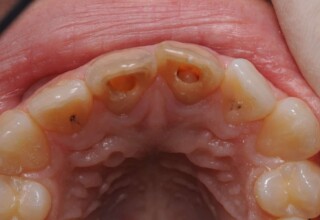

Δύσχρωμα απονευρωμένα δόντια

Μια ιδιαίτερη περίπτωση δύσχρωμων απονευρωμένων δοντιών που ο κεντρικός είχε βλάβη από εξωτερική απορρόφηση. Έγινε καθαρισμός του κεντρικού από την βλάβη και επειδή δεν μπορούσε να λευκανθεί λόγω της επαφής με τα ούλα, σφραγίστηκε σε πρώτη φάση, μετά λευκάνθηκε και στο τέλος έγινε η τελική αποκατάσταση.

Αρχική εμφάνιση

Τελική εμφάνιση